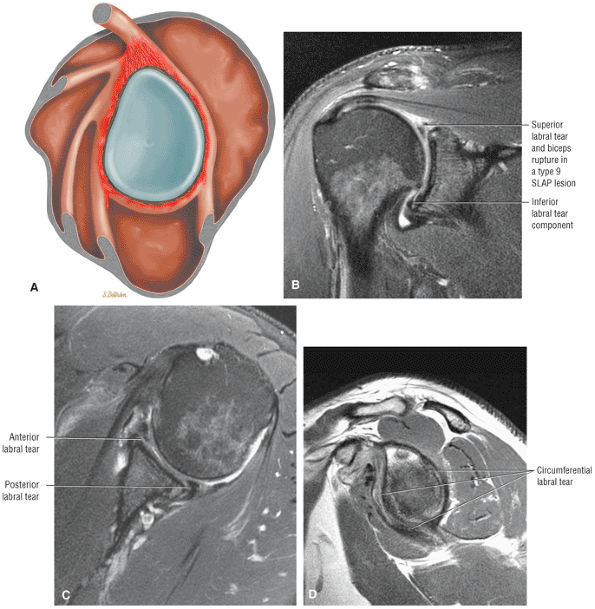

-

Subacromial keel spurs are located on the anteroinferior lateral portion of the acromion.

Acromial thickness is important in planning subacromial decompression procedures.

The AC joint may hypertrophy, but it is not responsible for true impingement.